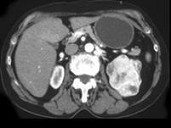

- 单项选择题男,54岁, 左侧腰痛伴间断性血尿2月余,结合CT图像, 最可能的诊断是 ( )

A、左侧肾癌

B、左侧肾血管平滑肌脂肪瘤

C、左侧肾上腺腺癌

D、左侧嗜铬细胞瘤

E、左侧肾盂癌